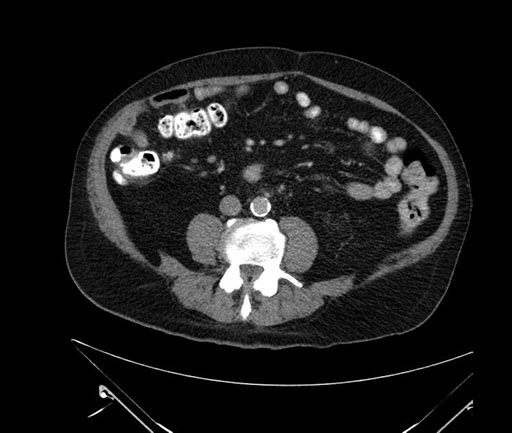

Whipple (pancreaticoduodenectomy) [case 7]

Imaging Analysis

Look through the patient's CT scan to identify any areas of concern for the necessary procedure.

Based on your CT findings, which issue(s) would give reason for "planned slowing down moment(s)" in this case?

Considering a standard Whipple procedure, what step(s) of the operation would you do differently in this case?